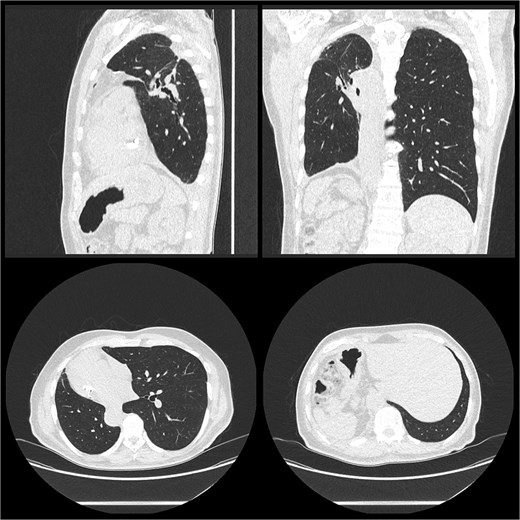

A 73-year-old gentleman was referred to our cardiothoracic department with a tumour of his right upper and right lower lobe diagnosed on computed tomography (CT), as seen in Fig. 1. He initially presented to his general practitioner (GP) with fatigue and weight loss. His background included ex-smoker with five pack-year history having quit 40 years prior, mild chronic obstructive pulmonary disease type 2 diabetes mellitus, dyslipidaemia, peptic ulcer disease, gastro-oesophageal reflux disease, diverticulosis, and colonic polyps. The patient has been known to have SIT since his early adulthood, an incidental finding on a chest X-ray.

A low-dose CT chest (Fig. 1) showed a nodule in the right upper lobe of 20 × 20 mm in diameter with a central solid component 7 × 4 mm and an 8-mm diameter ground glass opacity with a central solid dot in the right lower lobe. No lymphadenopathy was detected.